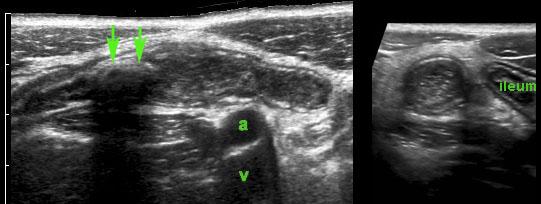

Viêm ruột thừa với sỏi phân trong lòng ruột thừa (mũi tên) được tìm thấy tại vị trí tắc nghẽn (a và v = động mạch và tĩnh mạch chậu).

Hình ảnh điển hình của ruột thừa viêm:

- mất nhu động

- cấu trúc phân lớp đồng tâm

- không thể ép xẹp

- đầu tận cùng bịt kín

- cấu trúc hình xúc xích

- ở vị trí cố định, thường tại vị trí đau tối đa

- đường kính tối đa trung bình là 11 mm (dao động từ 6 đến 25 mm)

- trong 35% trường hợp, sỏi phân trong lòng ruột thừa (mũi tên) được tìm thấy tại vị trí tắc nghẽn

Trong 6-12 giờ đầu, lòng ruột thừa giãn rộng rõ rệt với thành mỏng và chưa có hiện tượng viêm mô mỡ xung quanh.

Bệnh nhân này nhập viện với cơn đau quanh rốn dữ dội, cấp tính kéo dài 4 giờ và không có đau khu trú tại vị trí ruột thừa giãn (giai đoạn đau tạng).

Lưu ý hiện tượng phồng của ruột thừa căng vào thành bụng (đầu mũi tên) trong khi ép.

Những ruột thừa này dễ bị bỏ sót trong quá trình khám siêu âm, do không có đau khu trú và không có hiện tượng viêm mô mỡ.